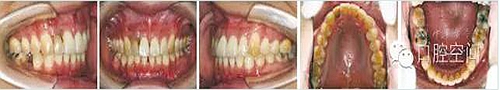

36歲男性患者,因前牙咬合過深影響上前牙種植修復(fù),尋求正畸治療改善咬合關(guān)系。直絲弓矯治器固定矯治半年后,雙側(cè)前磨牙鎖頜解除,下牙列排齊,更換至0.017英寸×0.025英寸鎳鈦絲。在下頜中切牙間前庭溝處,局麻下切開黏膜,正中聯(lián)合部位植入一枚微螺釘(1.6 mm×9 mm,慈北醫(yī)療器械有限公司)。通過直徑0.30 mm結(jié)扎絲連接微螺釘頭部,形成牽引鉤形狀,以微螺釘種植體支抗行閉合式牽引壓低下頜切牙。8個月后前牙覆頜正常。固定矯治19個月,右上中切牙種植修復(fù)完成,去除固定矯治器,進入保持階段?;颊呙骖M像及X線片見圖10,圖11,圖12,圖13,圖14,治療前后頭影測量結(jié)果見表3。

圖11病例2治療中像,以微螺釘支抗閉合式牽引壓低切牙改善深覆